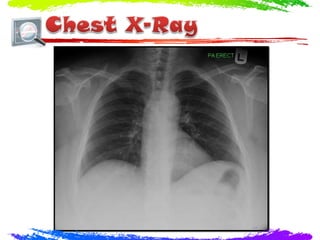

• #36 Findings Both lungs are clear The heart and mediastinum are normal. No pleural effusion could be identified Both CP angles are sharp No collapse or pneumothorax is noted The trachea is centralized The visualized bony structures show no gross abnormalities